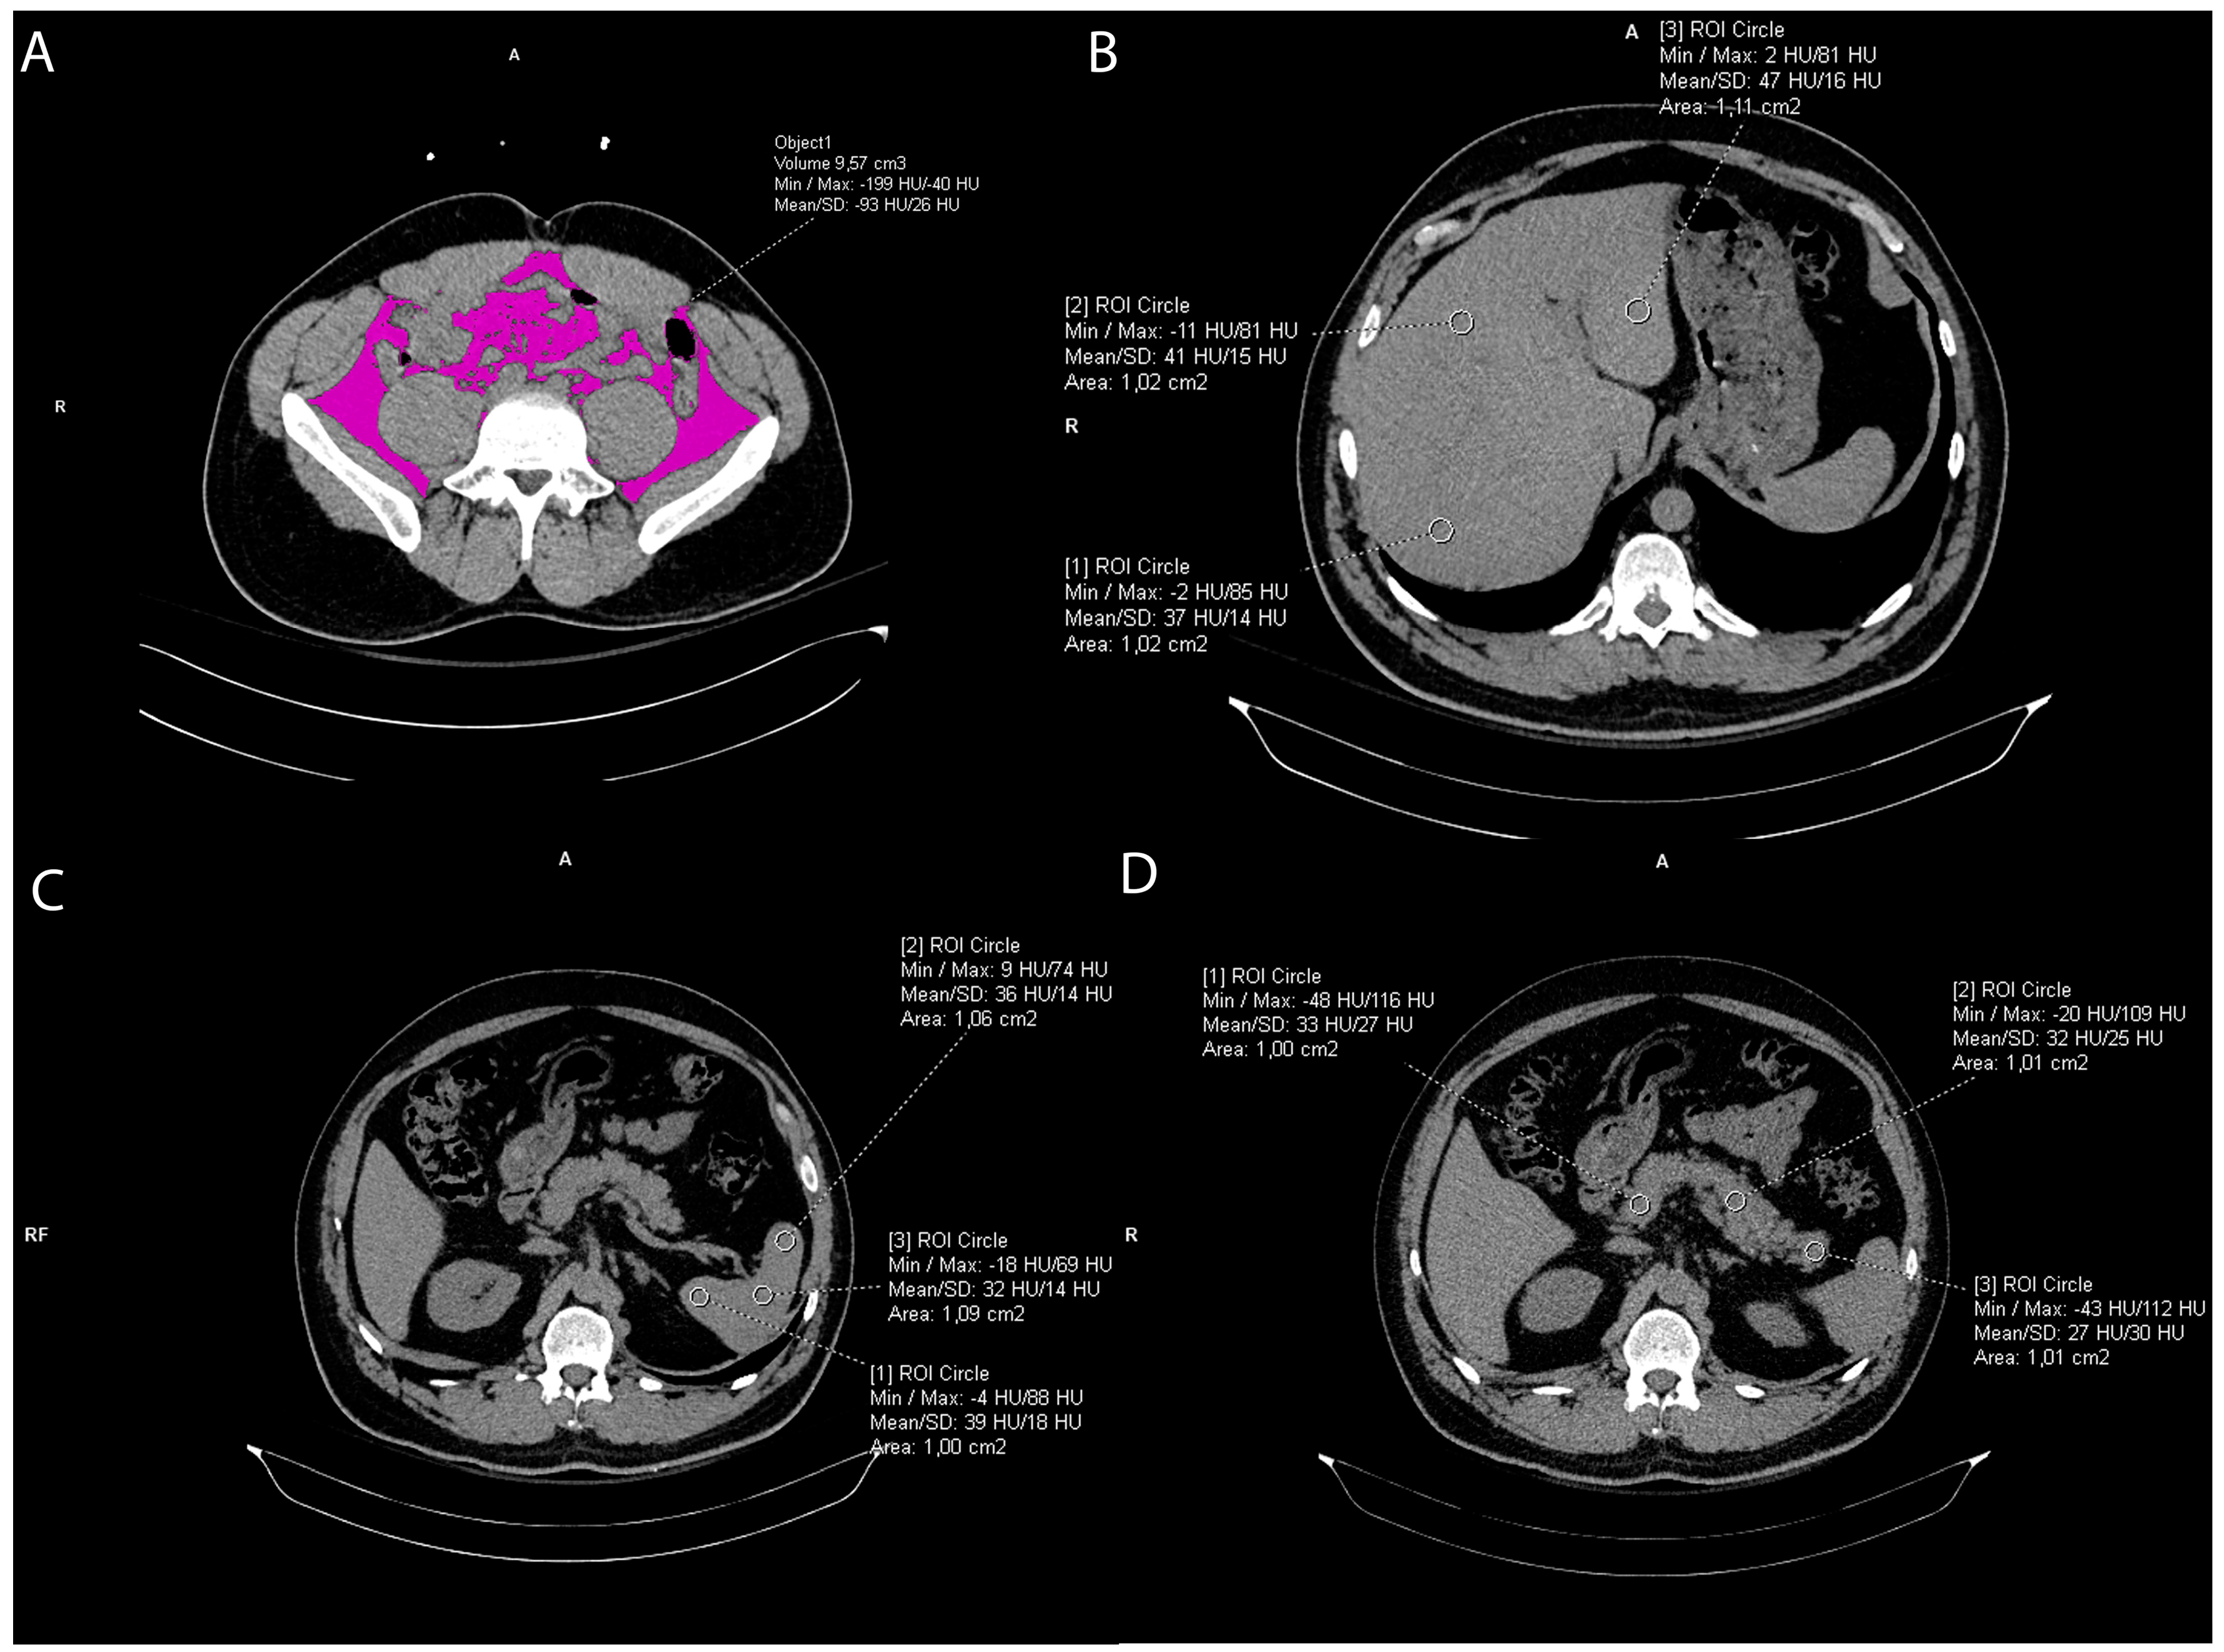

Figure 2. Representative axial CT images showing visceral fat volume calculation (A), liver attenuation measurement (B), spleen attenuation measurement (C), and pancreas attenuation measurement (D).

2.3. Liver and Spleen Attenuation Measurement

Liver CT attenuation was estimated by drawing three round regions of interest (ROI) of the approximately same size, 1 cm2, at the portal vein level within the left lobe, right anterior lobe, and right posterior lobe of the liver, respectively. All ROIs were carefully distributed in the liver parenchyma and the biliary, vascular, and extrahepatic structures were excluded. (Figure 2). The final liver attenuation measure was an average Hounsfield Unit (HU) at the three measurements sites. Spleen attenuation was similarly obtained by averaging three manually placed round ROIs (approximately 1 cm2) at three different areas of the same slice (Figure 3). The attenuation index, the liver-to-spleen attenuation ratio (L/S), was calculated by dividing average liver with average spleen attenuation, fi L is the hepatic attenuation and S is the splenic attenuation [21,22]. The index was used as a measure of liver fat accumulation (ectopic fat).

2.4. Pancreas Attenuation Measurement

Five ROIs were drawn over the uncinate process, the head, neck, body, and tail of the pancreas (Figure 2), while three ROIs were drawn in the spleen, as previously mentioned (Figure 2), [23,24]. In both organs, a circular ROI of 1 cm2 was drawn [24,25]. To ensure reproducibility of the measurements, the ROIs were manually placed in order to avoid vessels and parenchymal calcifications. An average of the ROIs was calculated and then the pancreas-to-spleen attenuation ratio (P/S) was determined by dividing the mean attenuation value of the pancreas with the mean attenuation value of the spleen. The pancreas-to-spleen attenuation ratio significantly correlated with pancreatic fat accumulation (pancreatic steatosis, ectopic fat) proven histopathologically [24,25,26,27,28].